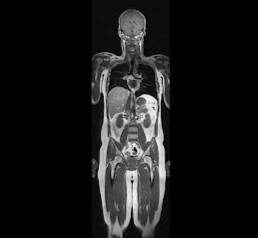

Магнитно-резонансная томография всего тела (Whole body MRI, check-up MRI) является скрининговым, комплексным обследованием всех органов и тканей организма за одну процедуру. 📌В отделении лучевой диагностики №2 данное исследование выполняется на современном МР-томографе Siemens Magnetom Aera 1,5 T и занимает около 50 минут.   🔵Методика обладает рядом важнейших преимуществ, таких как отсутствие лучевой нагрузки, раннее обнаружение асимптоматических очагов воспаления и новообразований, выявление аномалий развития различных органов, высокая разрешающая способность и качество изображений.   Данное исследование не требует какой-либо серьезной подготовки, во время исследования пациент находится в положении лежа на столе томографа, поверх всего тела будут расположены радиочастотные катушки. При необходимости во время исследования внутривенно может быть введено контрастное вещество для уточнения характера выявленных изменений. Противопоказания к проведению МРТ всего тела не отличаются от о

Магнитно-резонансная томография всего тела (Whole body MRI, check-up MRI) является скрининговым, комплексным обследованием всех органов и тканей организма за одну процедуру.

📌В отделении лучевой диагностики №2 данное исследование выполняется на современном МР-томографе Siemens Magnetom Aera 1,5 T и занимает около 50 минут.

🔵Методика обладает рядом важнейших преимуществ, таких как отсутствие лучевой нагрузки, раннее обнаружение асимптоматических очагов воспаления и новообразований, выявление аномалий развития различных органов, высокая разрешающая способность и качество изображений.

Данное исследование не требует какой-либо серьезной подготовки, во время исследования пациент находится в положении лежа на столе томографа, поверх всего тела будут расположены радиочастотные катушки. При необходимости во время исследования внутривенно может быть введено контрастное вещество для уточнения характера выявленных изменений.

Противопоказания к проведению МРТ всего тела не отличаются от ограничений к проведению любого другого МР-исследования.